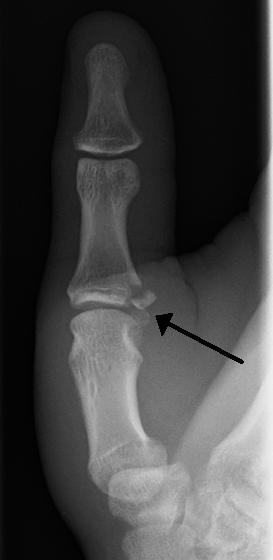

Gamekeeper's thumb

| Avulsion fractures of the ulnar base of the proximal phalanx of the thumb ( Gamekeeper's fracture ) | |

Gamekeeper's thumb (also known as skier's thumb or UCL tear) is a type of injury to the ulnar collateral ligament (UCL) of the thumb. The UCL is torn at (or in some cases even avulsed from) its insertion site into the proximal phalanx of the thumb in the vast majority (approximately 90%) of cases.[1] This condition is commonly observed among gamekeepers and Scottish fowl hunters, as well as athletes (such as volleyballers). It also occurs among people who sustain a fall onto an outstretched hand.

When approaching this type of injury, the physician must first determine whether there is an incomplete rupture (or sprain) of the UCL, or a complete rupture. If the UCL is completely disrupted, the physician must then determine whether there is interposition of the adductor aponeurosis (Stener lesion), or simply a complete rupture of the UCL with anatomic or near-anatomic position. Radiographs are helpful in determining the possible presence of an avulsion fracture of the proximal phalanx insertion site of the ulnar collateral ligament. Stress examination, or one done under fluoroscopic guidance, can help determine the integrity of the ligament.